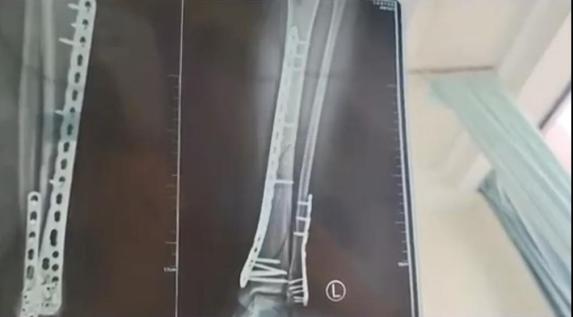

2024年,甘肃兰州的武女士发文称,她穿着鞋底厚达7厘米的增高洞洞鞋下楼,结果不慎崴脚摔倒,造成了左腿粉碎性骨折。武女士介绍,自己的这双洞洞鞋鞋底比较厚,脚掌中间又是凹进去的,她下楼梯时正好踩到了凹进去的地方,没踩稳,整个人的重心往前扑,重量都集中在了腿上。